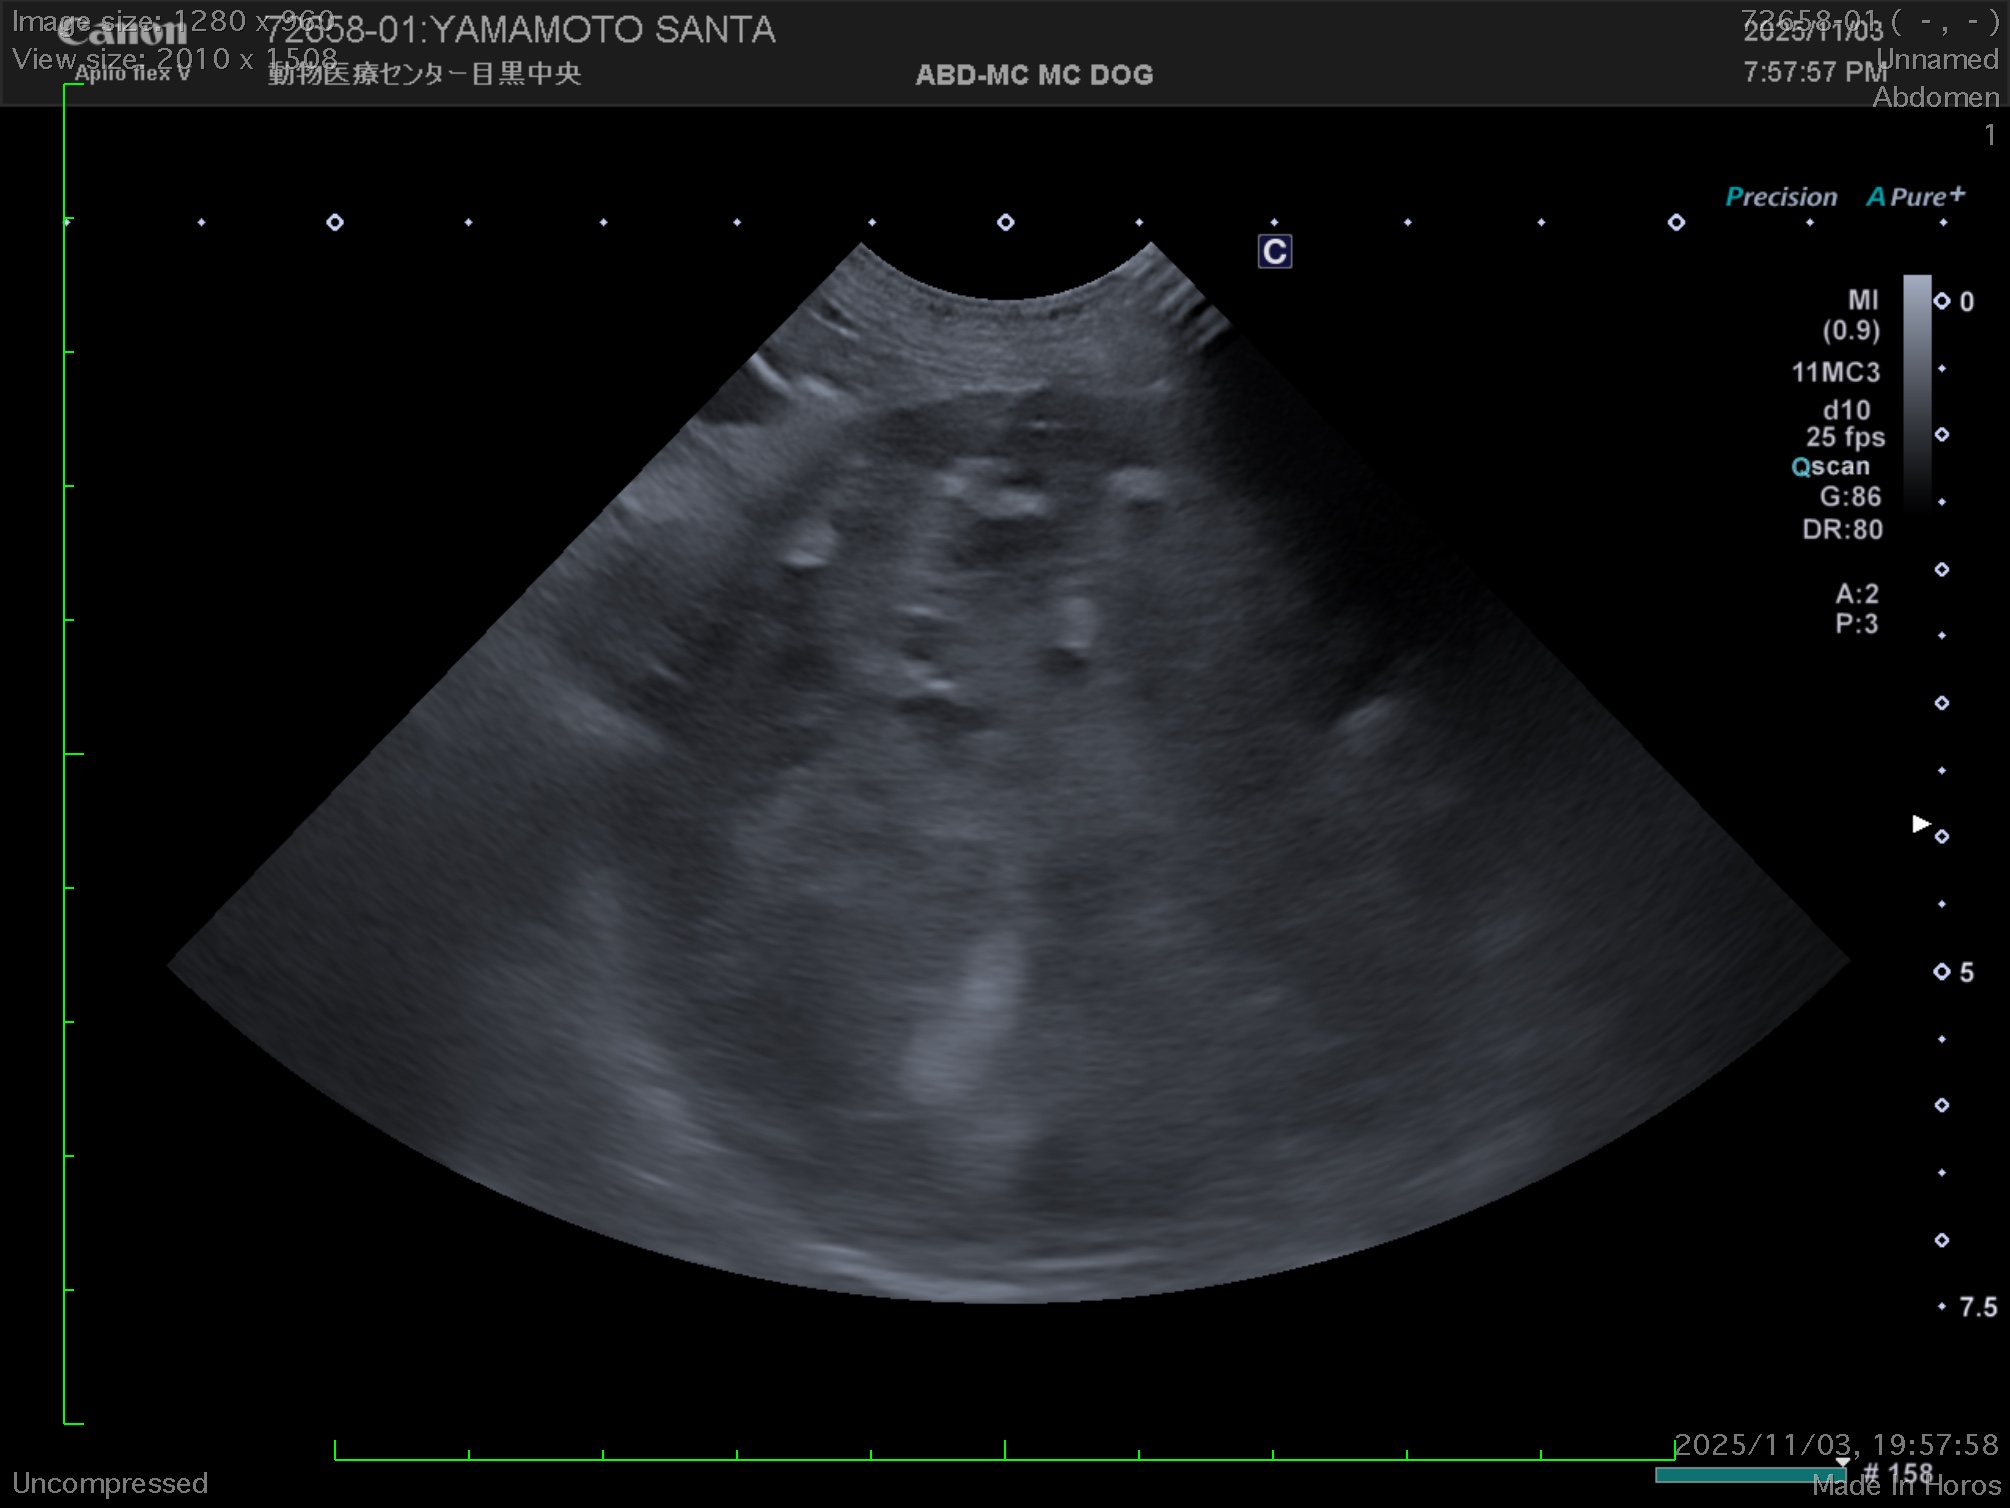

そしてその麻酔前検査(MRIは麻酔が必要となります)をしたところ、X線(レントゲン)検査にてお腹の中に巨大な腫瘍があることがわかりました。

緊急で詳細な検査を実施したところ、腫瘍はおそらく脾臓を起源としているだろうこと、また心臓にも腫瘍があることが残念ながら診断されました。

通常であれば、14歳のわんちゃんに手術を勧めることはあまりないのですが、今回の脾臓の腫瘍が破裂すると突然死を起こすこと(6~8cmもありました)、心臓の腫瘍が脾臓の腫瘍の転移ではなく別物の腫瘍であること(こちらは比較的進行がゆっくりな腫瘍と診断されました。)から、急遽CTにて全身の転移などがないことを確認し、開腹手術にて脾臓を摘出しました。